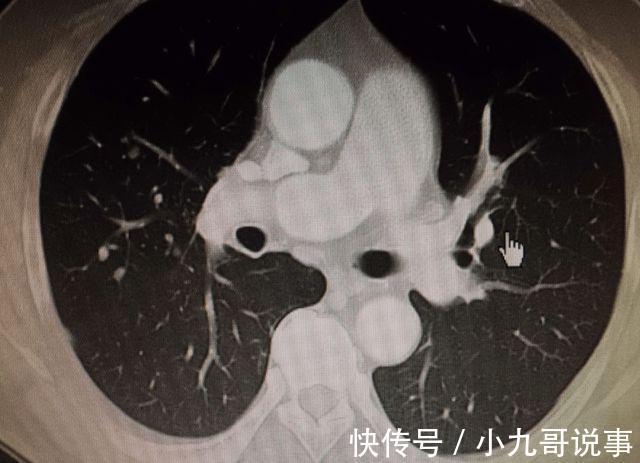

听完医生的解释之后马大姐便回家了,回到家中之后的马大姐也是严格按照医生的叮嘱调节自己的生活饮食习惯,并且过了一段时间之后再次去医院进行复查时,医生告诉马大姐,她的结节已经消失不见了。

听到医生说这节消散了之后,马大姐悬着的心也可谓是放下了,在旁边看病的病友都感到非常的好奇,想要知道马大姐在平时是怎样做的,能够让姐姐在半年时间当中消散,马大姐也是大方的与大家分享了自己的经验。